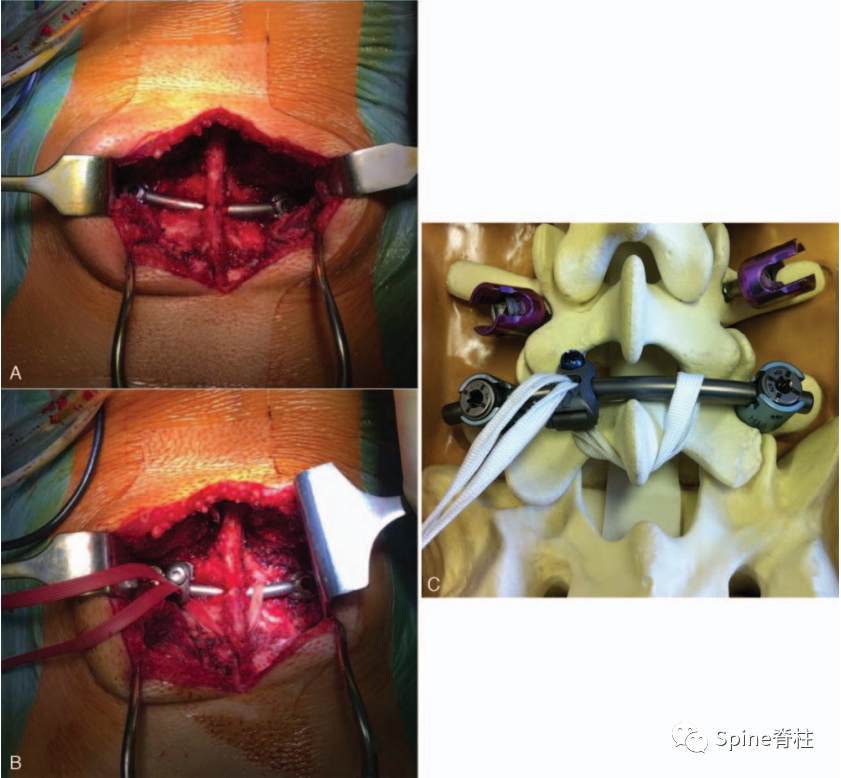

随着内固定的发展,既往峡部单纯修复植骨因融合率低、卧床时间长,现已很少应用。而植骨修复并节段固定有多种方法,包括Scott接线法、Buck螺钉法、Louis的蝶形板、钉钩技术(椎弓根螺钉和钩-棒系统)、U形棒等。从临床角度看,钉钩技术可以用刚性植入物固定断裂的峡部,并沿椎板方向施加作用力,有效稳定峡部,这对于达到更好的骨性愈合是至关重要的。理论上,此种方法更符合生物力学,对邻近节段影响小,但应把握好适应症,建议单纯腰椎峡部裂伴或不伴轻度滑脱患者可行植骨修复并节段固定。

1. 椎弓根螺钉-钉钩系统

PMID: 9199377

PMID: 15699811

PMID: 17520298

2022年,解放军总医院第三医学中心彭宝淦(我的硕导和博士后合作导师)和李端明主任提出了一种新型解剖型钉钩椎弓根螺钉系统。根据腰椎解剖,棘突与椎板成一定角度,椎板向后向上倾斜,椎板下缘和椎弓根螺钉尾部与矢状面成一定角度。根据上述解剖特征,解剖型钉钩椎弓根螺钉系统的钩和棒在这三个方向上都是倾斜的。钩棒与椎板完全匹配,有利于将钉钩安装在椎板的下缘,且易于将棒与万能椎弓根螺钉连接。此外,该系统可通过肌间隙入路置入。

PMID: 35979102